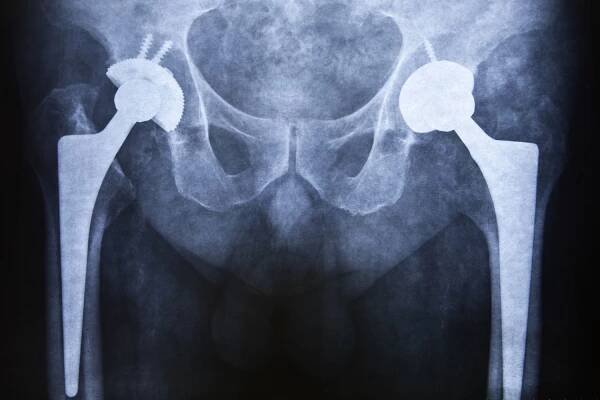

Operace kyčle se provádí za účelem náhrady poškozeného nebo opotřebovaného kyčelního kloubu umělou náhradou. Během zákroku se odstraní poškozené části kloubu a nahradí se komponenty z kovu, keramiky nebo plastu. Tento proces pomáhá obnovit funkci kloubu a zmírnit bolest. Operace se provádí pod celkovou nebo…

Totální endoprotéza kyčle (TEP) je chirurgický zákrok, při kterém je nahrazena poškozená kyčelní kloubní část umělou náhradou, tzv. endoprotézou...

Náhrada kyčle patří v současné době k nejčastějším operačním výkonům v ortopedii. Je metodou volby u pacientů s pokročilým stupněm artrózy (III. a vyšší stupeň), po zlomeninách krčku a nekrózy hlavice stehenní kosti.